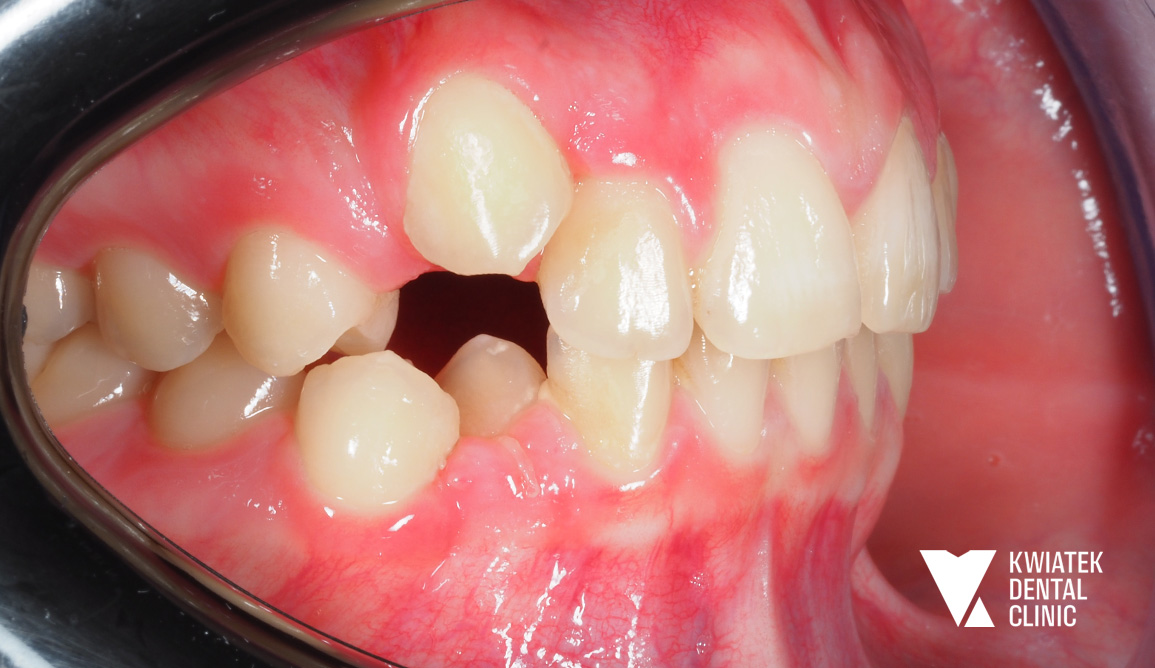

Leczenie rozpoczęto od szczegółowej konsultacji ortodontycznej oraz pełnej diagnostyki obejmującej zdjęcie pantomograficzne, cefalometryczne oraz skan wewnątrzustny.

W badaniu stwierdzono:

Już na etapie diagnostyki wskazano konieczność leczenia interdyscyplinarnego obejmującego zarówno ortodoncję, jak i intensywną poprawę higieny jamy ustnej.

Przed rozpoczęciem właściwej terapii Pacjentka została skierowana na profesjonalną higienizację wraz z instruktażem higieny. Ze względu na obecność licznych złogów nazębnych, osadów oraz demineralizacji szkliwa, etap przygotowawczy miał kluczowe znaczenie dla bezpieczeństwa leczenia.